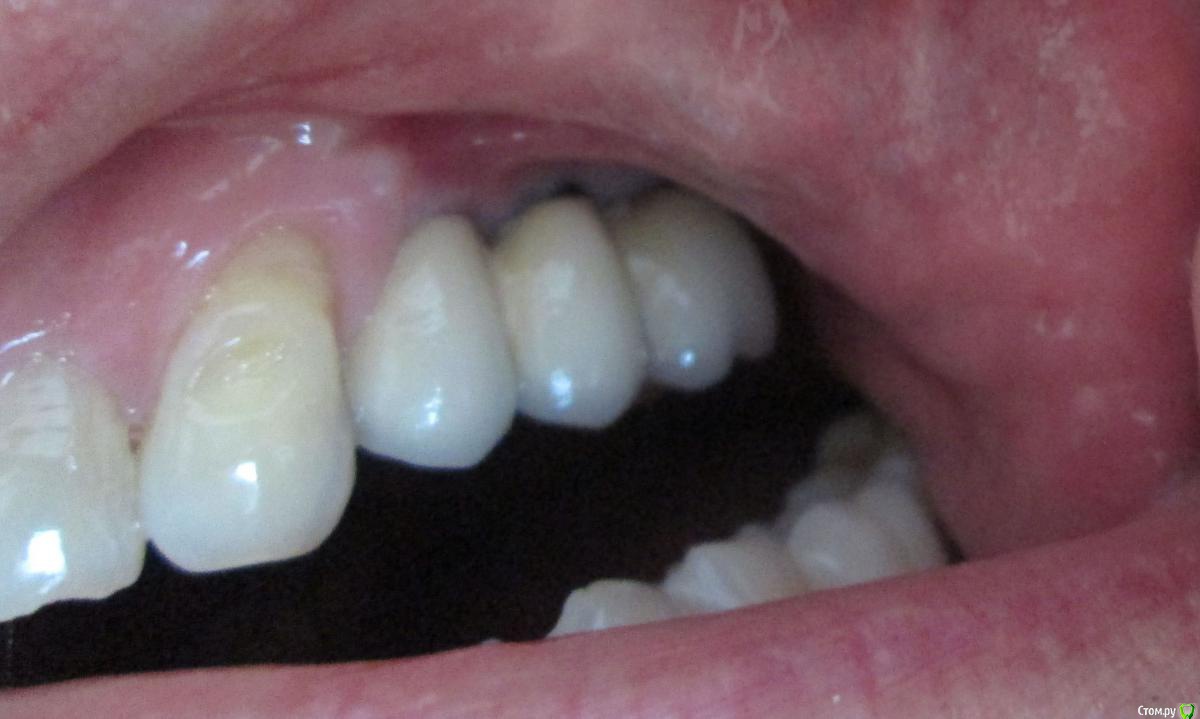

Evikrol Опубликовано 22 марта, 2017 Поделиться Опубликовано 22 марта, 2017 Сфотографируйте коронки Ссылка на комментарий

filvik Опубликовано 23 марта, 2017 Автор Поделиться Опубликовано 23 марта, 2017 (изменено) Сфотографируйте коронкиКак-то, так. Изменено 23 марта, 2017 пользователем filvik Ссылка на комментарий

filvik Опубликовано 26 марта, 2017 Автор Поделиться Опубликовано 26 марта, 2017 решить вопрос с мягкими тканями. И с костью все будет ок.Обьясни , пожалуйста.Эта коронка с фото (ракурс подкачал, вид как-бы с низу),установлена после наращивания кости и мягких тканей.До операции было 3 коронки (пролежни и тд и тп),это первая коронка в этом году после операции. Ссылка на комментарий

Bier Опубликовано 26 марта, 2017 Поделиться Опубликовано 26 марта, 2017 я вижу на фото дефицит кератинизированной десны и тонкий биотип. Вот это надо поменять и все станет стабильнее.У нас принято общаться на Вы с незнакомыми. 1 Ссылка на комментарий